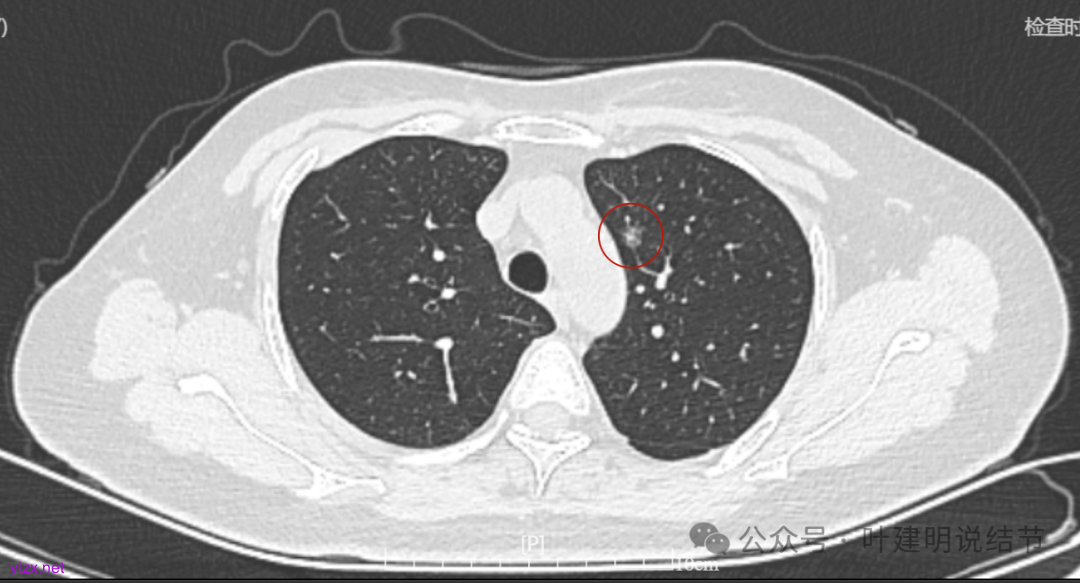

1.2021年12月因感冒咳嗽做了胸部CT,显示多发结节。有大的0.7*0.5cm。

2.2022年5月2日复查增强CT,显示肺结节0.7*0.6cm

4.2022年7月31日做了ct复查,报告显示结节增大,0.8*0.7cm。

病灶7:右下叶胸膜下淡而微小的磨玻璃结节,考虑肺泡上皮增生可能性大。

两肺多发结节,持续存在,总体上看,瘤肺边界清,轮廓清楚,主病灶有血管穿行,表面也不平,考虑微浸润性腺癌可能性大,其他2处不典型增生或原位癌可能性大些。总的来说,风险还不大,也不会引起胸痛症状,但因两侧都有,且可能后续均是要手术的,个人觉得左侧病灶可以考虑先切除,因为两个病灶离得不远,总的来说还是靠边缘的,定位后楔形切除能将两处都切了。这样只需再关注右侧的,以后真右侧也要手术,也可拉长两次手术的间隔时间,有利于恢复以及耐受性会好些。两侧同时手术,疼痛、咳嗽、恢复情况容易差些,也容易合并肺炎或其他并发症,安全性差一点的。以上意见供参考!